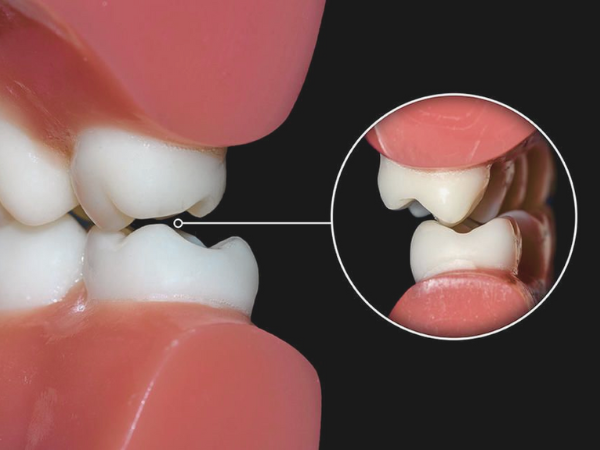

– 교합 조정으로 개선

![마곡역치과_4. 인레이 치료 후 통증 생기는 이유 [ 자연스러운 회복? 문제 신호?] 관련 이미지 2](https://pub-9f2bb3498faf4d1d8714b41df24753e3.r2.dev/content/clinics/archive/rlg13v0fli/naver_blog/dia_dental/assets/by_hash/fa7ea1e32eccbdfef79e11f8f9d742e8999a2c08369dd1dc25ef192bc30a3398.png)

마곡역치과_교합

두 번째는 ‘높이 문제’입니다.

인레이가 아무리 정밀하게 제작돼도

환자분 고유의 교합 습관, 근육 사용 강도에 따라

딱 맞지 않고 한쪽으로 힘이 쏠릴 수 있습니다.

그래서 씹을 때 특정 부위가 쿡쿡 눌리는 느낌

아침에 통증이 없는데, 하루가 갈수록 아픔이 심해지죠

한쪽으로만 씹고 싶어난 통증의 특징이 있습니다.

이건 절대 참고 넘기면 안 됩니다.

교합 조정 한 번으로 통증이

바로 사라지는 경우도 많기 때문입니다.

불편감이 2~3일 이상 지속된다면

치과에서 교합 상태를 다시 체크받아보세요.

‘높이’ 하나 바꿨을 뿐인데

통증이 거짓말처럼 사라지는 경우, 생각보다 많습니다.